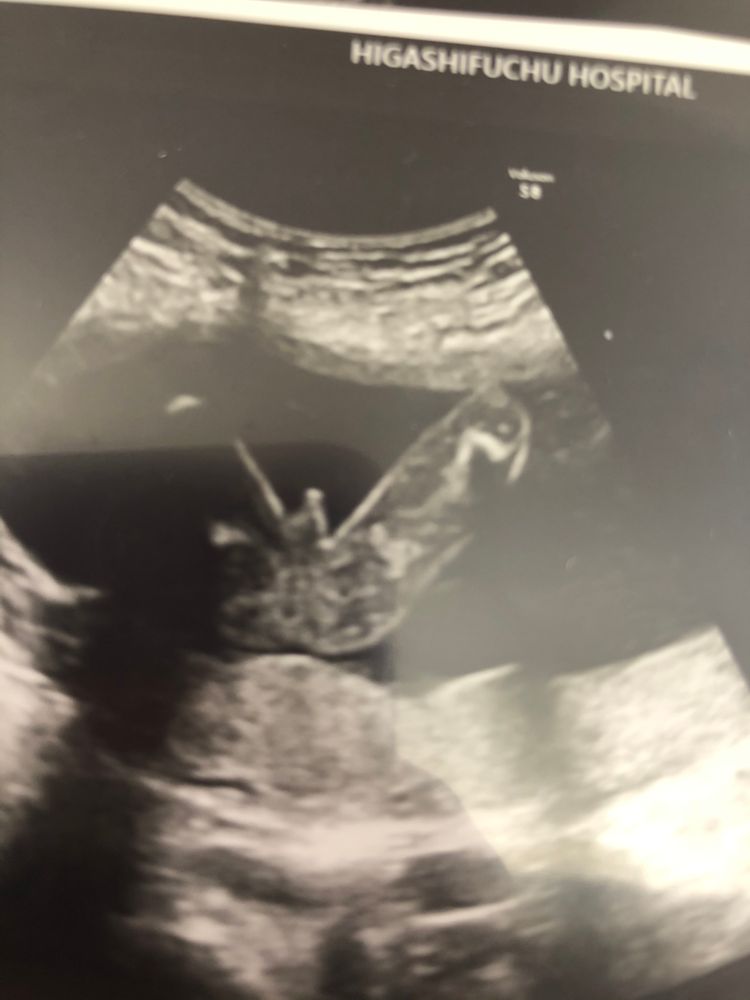

В ожидании чудаСегодня на сроке 20 недель и 4 дня меня наконец-то выписали из больницы домой и я прошла скрининг ( в Японии скрининг есть не во всех больницах и проводится по желанию. Вообще, что есть что-то похожее на скрининг есть я узнала только в эту беременность. И сразу записалась, так как стоит недорого около 40 долларов. Биохимию крови не делают, только узи.) По результат узи все хорошо.Впервые узнала , что прикрепление по задней стенке. Единственное бпр на 21 неделю, все остальные параметры на 20 недель,но не знаю насколько это критично . И потом все азиатские малыши большеголовые .Малыш весит уже примерно 332 грамма. Сказали пол... это 100 процентно мальчик.( врач даже распечатала фотографию мужского достоинства, вместо обычного фото узи 😂)